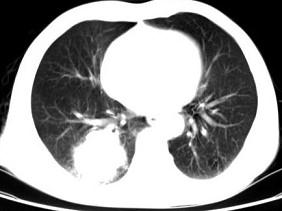

问题 男,66岁,胸痛一月,胸部CT如图,最可能的诊断是 ( )

选项 A、右下肺错构瘤 B、右侧炎性假瘤 C、右下肺动静脉瘘 D、右下肺肉瘤 E、右下肺周围型肺癌

答案 E